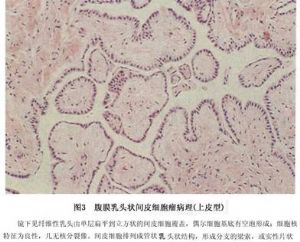

(2)上皮样间皮瘤:上皮样间皮瘤瘤细胞呈立方形或多角形,常有脉管状或乳头状结构。上皮性间皮瘤最多见于弥漫性间皮瘤中,瘤细胞呈不同的分化状态,可形成高分化管状或乳头状结构,也可呈未分化的片块状瘤组织,瘤细胞大小不一,呈实性,为结缔组织所包绕。管状乳头状结构的瘤组织构成腺样、管状或者囊性,内衬以立方或扁平的上皮样细胞,细胞大小一致,空泡状核,可见1~2个核仁。胞浆丰富,细胞轮廓清楚。肿瘤亦可呈裂隙状或形成大小不等的囊腔,内衬以扁平的上皮细胞,这些裂隙内有时可见乳头状突起。类似乳头状腺癌。有些病例,瘤细胞排列成实性、条索状或者巢状,无腺样或乳头状结构。但有时瘤组织周围可有黏液物质,形成类似黏液湖的结构。细胞形态比较一致,核大小不一,胞浆内时有空泡形成,含有黏多糖类物质(图3)。

(2)上皮样间皮瘤:上皮样间皮瘤瘤细胞呈立方形或多角形,常有脉管状或乳头状结构。上皮性间皮瘤最多见于弥漫性间皮瘤中,瘤细胞呈不同的分化状态,可形成高分化管状或乳头状结构,也可呈未分化的片块状瘤组织,瘤细胞大小不一,呈实性,为结缔组织所包绕。管状乳头状结构的瘤组织构成腺样、管状或者囊性,内衬以立方或扁平的上皮样细胞,细胞大小一致,空泡状核,可见1~2个核仁。胞浆丰富,细胞轮廓清楚。肿瘤亦可呈裂隙状或形成大小不等的囊腔,内衬以扁平的上皮细胞,这些裂隙内有时可见乳头状突起。类似乳头状腺癌。有些病例,瘤细胞排列成实性、条索状或者巢状,无腺样或乳头状结构。但有时瘤组织周围可有黏液物质,形成类似黏液湖的结构。细胞形态比较一致,核大小不一,胞浆内时有空泡形成,含有黏多糖类物质(图3)。